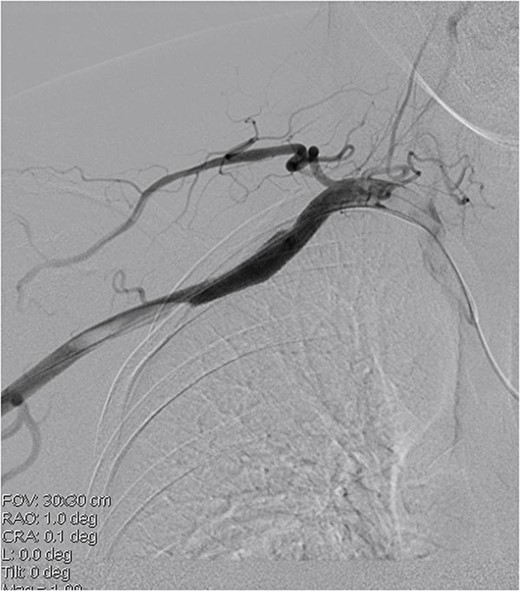

A 45-year-old female patient presented with a 20-day history of acute onset cooling, pallor, and paresthesia in the right upper limb along with supraclavicular discomfort on the right side. Notably, the patient’s medical history was devoid of significant conditions such as atrial fibrillation, hypertension, or coronary artery disease. Physical examination revealed a marked decrease in skin temperature, the absence of palpable radial and brachial pulses, and pallor in the affected extremity, with no detectable neurological deficits. Vascular ultrasonography revealed arterial thrombosis extending from the subclavian artery to the distal brachial, radial, and ulnar arteries. Computed tomographic angiography further characterized these findings, identifying filling defects in the right axillosubclavian vasculature indicative of a substantial clot burden. Intraprocedural digital subtraction angiography (DSA), conducted to facilitate endovascular thrombectomy, revealed a 12 × 12 mm pseudoaneurysm originating from the axillary artery (Fig. 1). The definitive treatment involved the deployment of an 8 × 60 mm (Fluency, Bard, USA) covered stent graft across the lesion in the vessel, followed by Fogarty balloon thrombectomy to re-establish distal perfusion (Fig. 2). Postoperatively, the patient received aspirin and short-term anticoagulation. Follow-up at 6 months, including clinical and ultrasonographic evaluations, confirmed symptom improvement, pulse restoration, and absence of ischemic or stent-related complications.

Covered stent placement isolates the pseudoaneurysm rupture, and further thrombectomy treatment is planned.